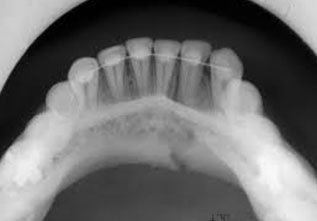

OCCLUSAL VIEW

Occlusal X-rays show the roof or floor of the mouth and are used to find extra teeth, teeth that have not yet erupted through the gums, jaw fractures, a cleft palate, cysts, abscesses or growths. Occlusal X-rays may also be used to find the position of any foreign object accidently entrapped into upper & lower jaws.